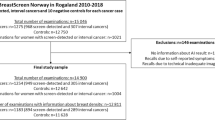

A consecutive subcohort from the prospective population-based Malmö Breast Tomosynthesis Screening Trial [13], consisting of 9581 women aged 40–74 (mean age 57.6 ± 9.5) with double-read screening mammograms, was included. The screening intervals were 1.5 years until the age of 55 and thereafter biennial screening. The subcohort consisted of a consecutive inclusion of trial participants with two-view digital mammograms (Mammomat Inspiration, Siemens Healthcare GmbH) for which both raw and processed imaging data were available (February 2012 until May 2015). Of the 9581 women, 255 were recalled (recall rate 2.7%) resulting in 68 screen-detected cancers (cancer detection rate 7.1/1000) and 187 false positives. Ground truth was based on histology of surgical specimen or core-needle biopsies and with a cross-reference to a regional cancer register. A normal mammogram was defined as free of screen-detected cancer. Participants in the Malmö Breast Tomosynthesis Screening Trial were also examined with tomosynthesis, but for the purpose of this study, only the independent mammography reading results were taken into account.

The distribution of risk scores for all mammograms, screen-detected cancers, and false positives is shown in Fig. 1. The cancer incidence in mammograms with low- and high-risk scores was 1.4/1000 and 13.6/1000, respectively. If mammograms with a risk score of 1 and 2 were to be excluded, 1829 (19.1%; 95% CI 18.3–19.9) normal exams could be removed, including 10 (5.3%; 95% CI 2.1–8.6) false positives, without missing a single cancer (Table 1). Half (53.0%, 95% CI 52.0–54.0) of the screen exams had low-risk scores (≤ 5). If these were to be excluded from screen reading performed by radiologists, seven (10.3%; 95% CI 3.1–17.5) cancers would have been missed, and 52 (27.8%; 95% CI 21.4–34.2) false positives would have been avoided. All seven cancers with low-risk scores were invasive (Table 2), of which three were small (≤ 7 mm), low-grade invasive tubular carcinomas, i.e. tumours with excellent prognosis [19]. On the other hand, three cancers, two ductal and one lobular type, were large (20 mm), one of which was histologic grade 3, i.e. of less-favourable prognosis. The radiologists’ consensus panel judged all cancers, except one, to be clearly visible (Fig. 2). The latter was a 20-mm-large mammographically occult invasive ductal carcinoma that was recalled due to an imaging finding of a pathologically enlarged lymph node. Six of the cancers had a radiographic appearance of a spiculated mass. All, except one, of the women with AI-missed cancers had dense breasts (Breast Imaging Reporting and Data System-category C and D [21]).